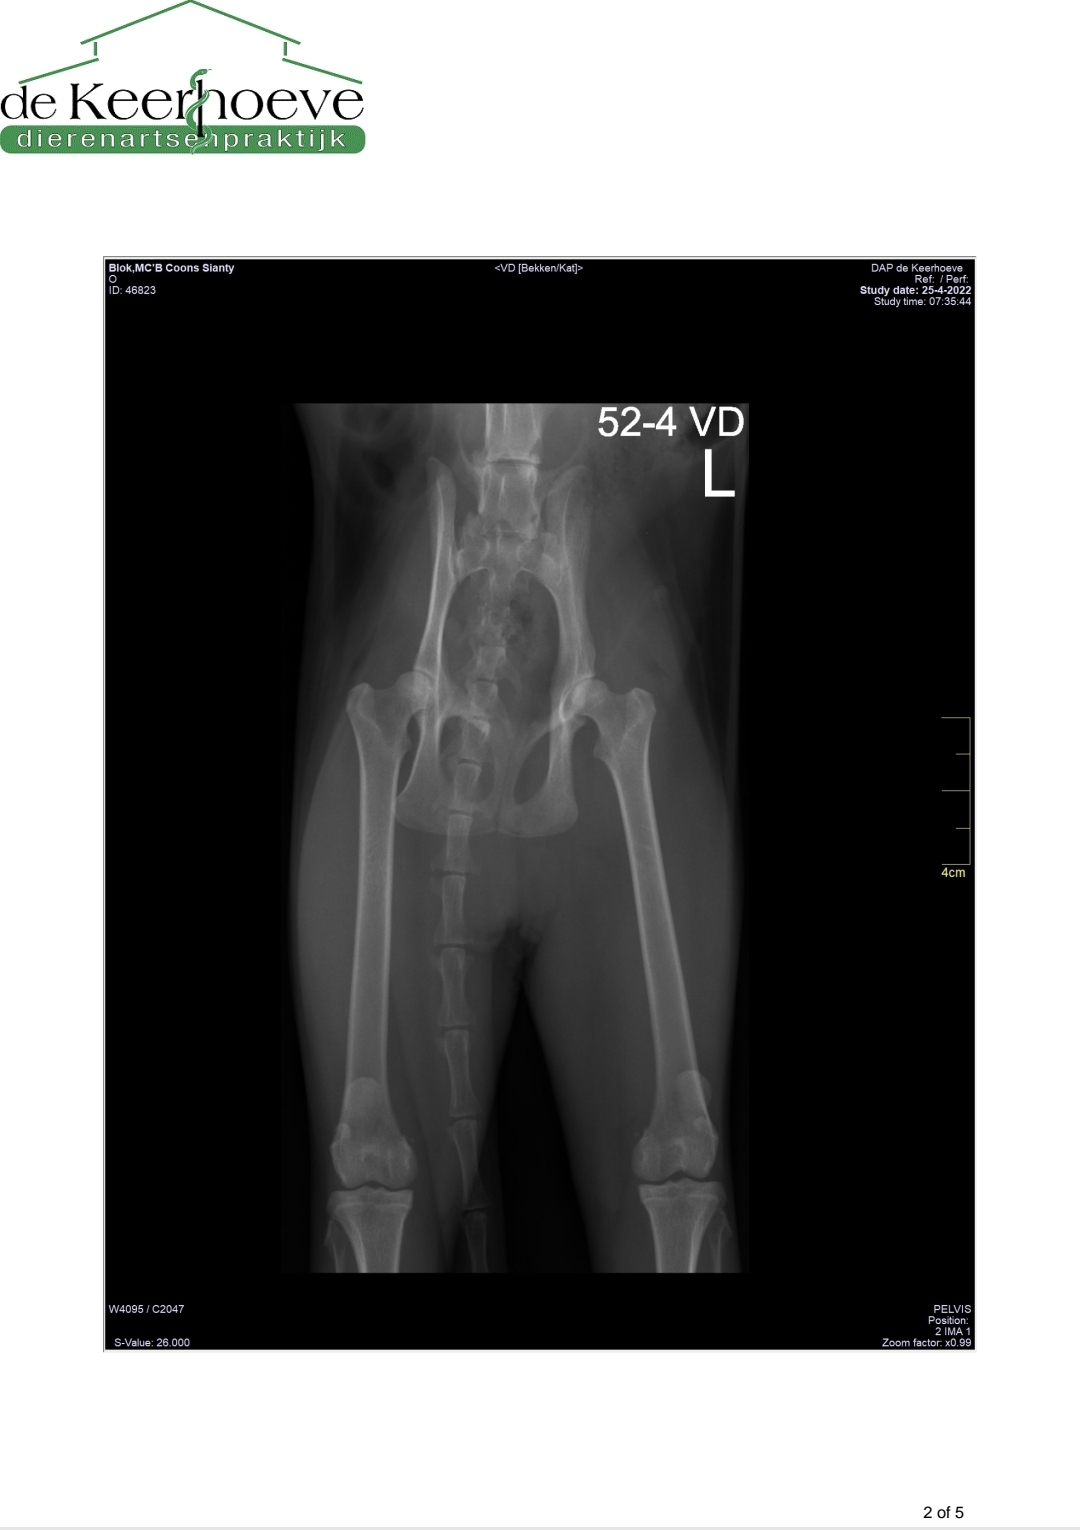

Fia Saura screen PL - HD

Afbeelding – 64,3 KB 374 downloads